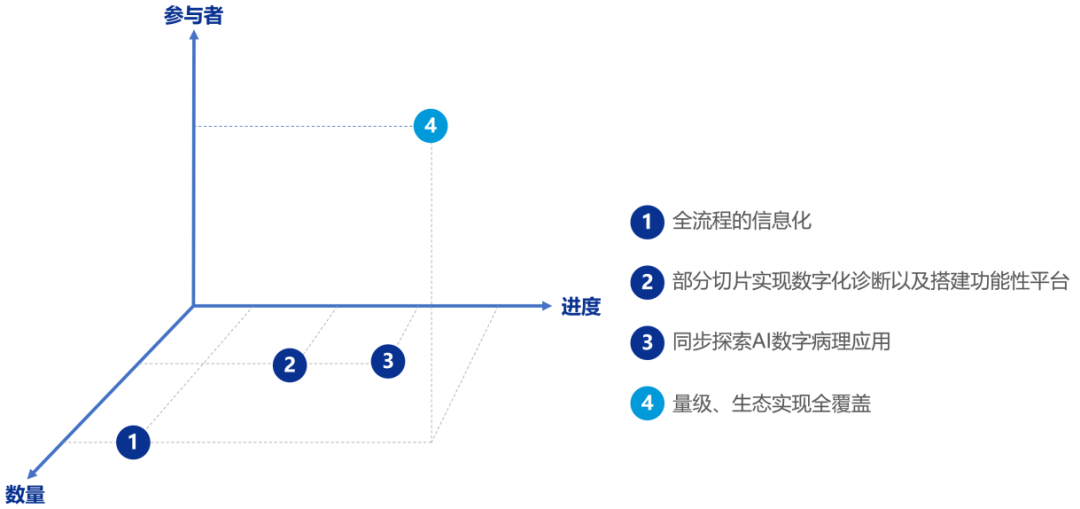

数字化智慧病理科建设指南:分级建设是核心主旨

分级建设方案